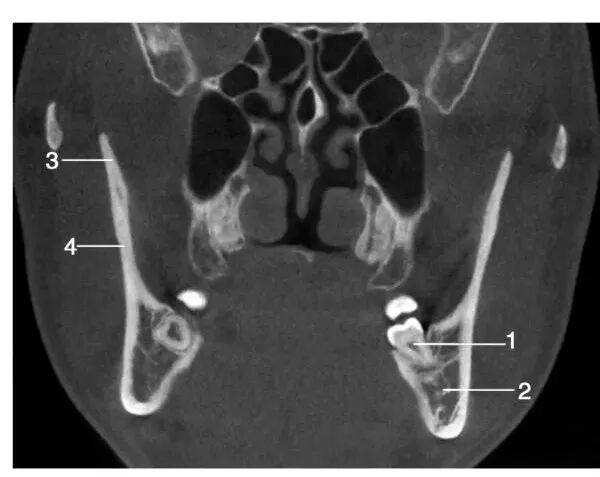

经下颌第三磨牙处层面冠状位图像

1.左下第三磨牙 ; 2.下颌神经管; 3.喙突 ;4.下颌升支